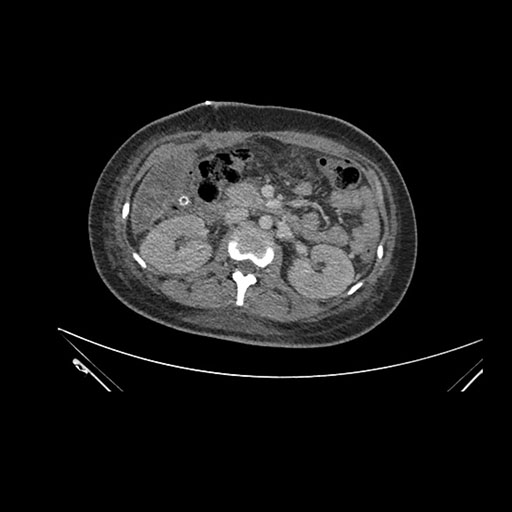

Imaging Analysis

Look through the patient's CT scan to identify any areas of concern for the necessary procedure.

Coronal Arterial

Based on initial findings, which issue(s) would you be most concerned about?